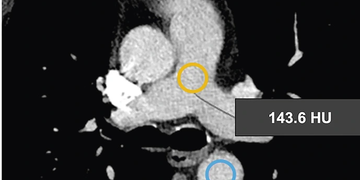

Die beiden nachfolgenden Monitoringbilder veranschaulichen deutlich den Unterschied der Kontrastierung beim Einsatz des Contrast Boosters.